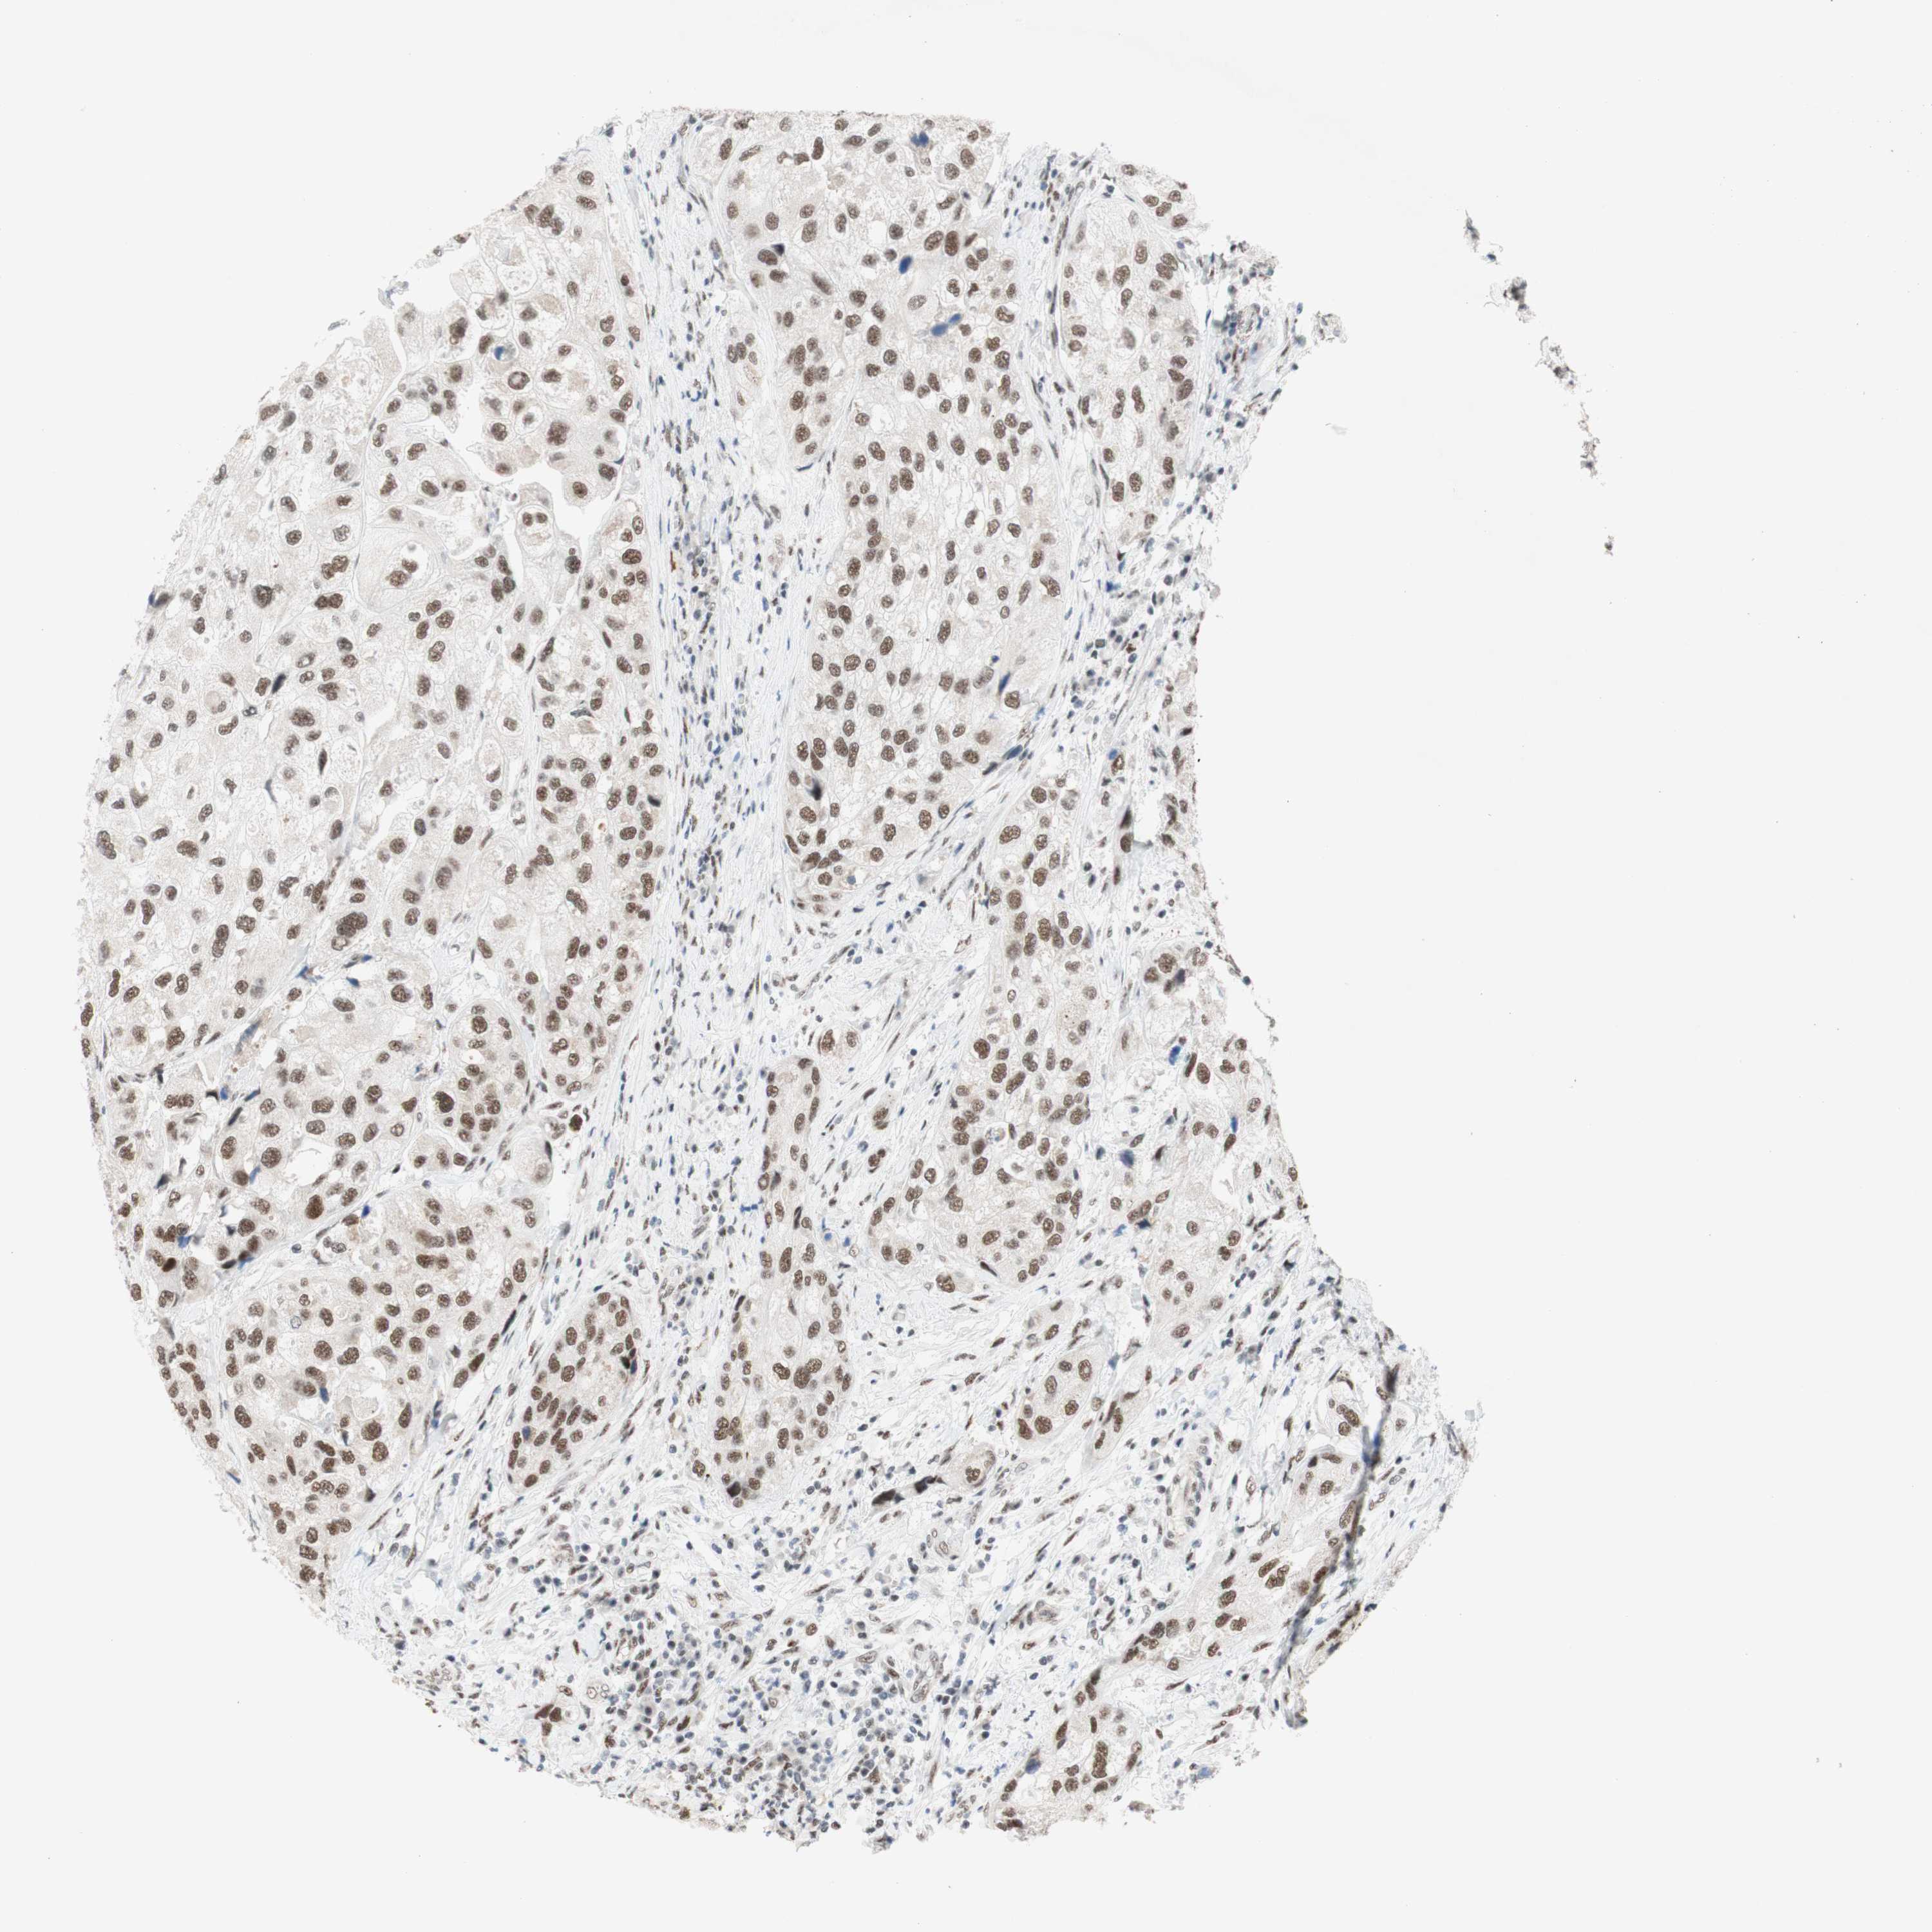

UROTHELIAL CANCER - Protein expressioni

A mouse-over function shows sample information and annotation data. Click on an image to view it in a full screen mode. Samples can be filtered based on level of antibody staining by selecting one or several of the following categories: high, medium, low and not detected. The assay and annotation is described here.

Note that samples used for immunohistochemistry by the Human Protein Atlas do not correspond to samples in the TCGA dataset.

Antibody stainingi

Antibody staining in the annotated cell types in the current human tissue is reported as not detected, low, medium, or high, based on conventional immunohistochemistry profiling in selected tissues. This score is based on the combination of the staining intensity and fraction of stained cells.

Each image is clickable and will lead to virtual microscopy that enables deeper exploration of all samples and also displays staining intensity scores, fraction scores and subcellular localization as well as patient and tissue information for each sample.

Antibody HPA038051

Antibody HPA059070

Antibody CAB012448

Staining

High

Medium

Low

Not detected

Intensity

Strong

Moderate

Weak

Negative

Quantity

>75%

75%-25%

<25%

None

Location

Nuclear

Cytoplasmic/membranous

Cytoplasmic/membranous,nuclear

Urothelial carcinoma, High grade

Urothelial carcinoma, Low grade

Urothelial carcinoma, NOS